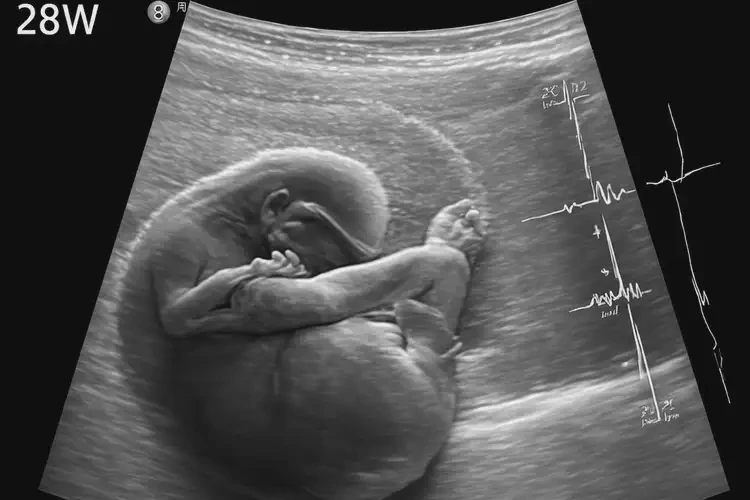

孕28周3天胎心184還要保胎嗎

胎心率184次/分鐘

對于孕28周3天的胎兒來說,胎心率184次/分鐘偏高,但是否需要保胎需綜合多方面因素判斷。

孕28周3天胎心184還要保胎嗎(圖1)